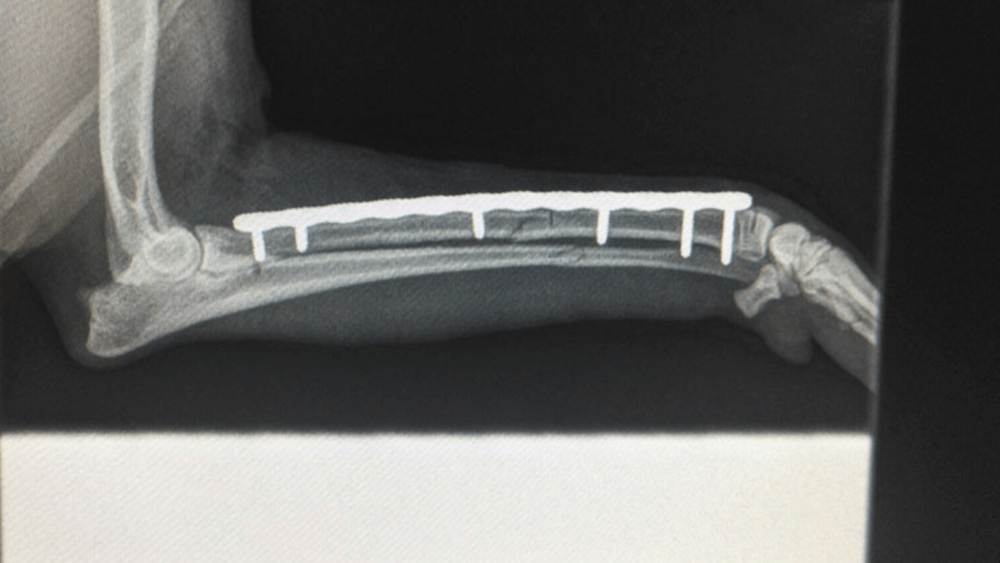

Metatarsal Plating

Example of metatarsal plating.